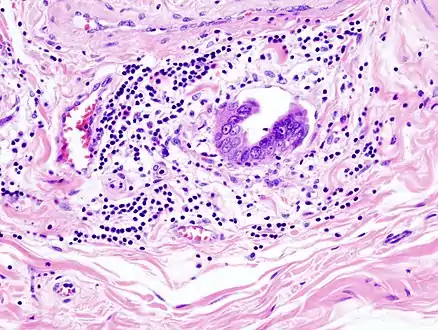

Gallbladder adenocarcinoma lymphatic invasion histopathology

Incidentally discovered gallbladder cancer (adenocarcinoma) following a cholecystectomy.